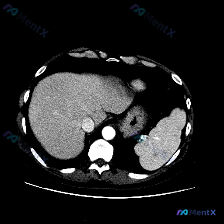

最近看到一份有意思的影像资料,不是因为发现了典型病变,而是恰恰相反——预设了“脾脏病变”的问题,但图像里却找不到明确异常。整理一下思路分享给大家。 --- 一、先看影像信息(单帧上腹部CT软组织窗横断面) 直接说客观看到的: 1. 肝脏:轮廓尚平滑,肝叶比例正常,实质密度大致均匀,肝内血管走形正常,...

看到一个很有意思的“预设型”病例,整理一下思路和大家分享。 临床背景与影像资料 这次的情况有点特别:临床提示关注“脾脏病变”,但提供的是一张单张的腹部CT横断面软组织窗图像。 先说说图像里能看到的: - 肝脏:实质密度均匀,无局灶性占位,边缘光滑,肝叶比例正常; - 脾脏:位于左侧,形态、大小在本断...

整理了一份挺有意思的影像读片案例,核心不是“是什么病变”,而是“如何面对前提与证据的冲突”。 影像资料基础 - 检查方式:上腹部增强CT(横断面,软组织窗) - 图像质量:清晰,无明显伪影,对比剂充盈良好 - 显示范围:上腹部层面,包含肝脏、胃、脾脏、腹主动脉及部分腰椎 客观影像表现 1. 肝脏:形...

今天看到一个很有意思的影像案例,用户一开始就预设了「脾脏病变」的存在,但当我仔细看完这张单层面的上腹部CT平扫后,发现结论可能和预设不太一样。整理一下思路和大家分享。 --- 先看影像基础信息 这是一张上腹部CT横断面软组织窗图像,层面清晰,软组织对比度良好,没有明显运动或金属伪影。能看到肝脏、胃、...